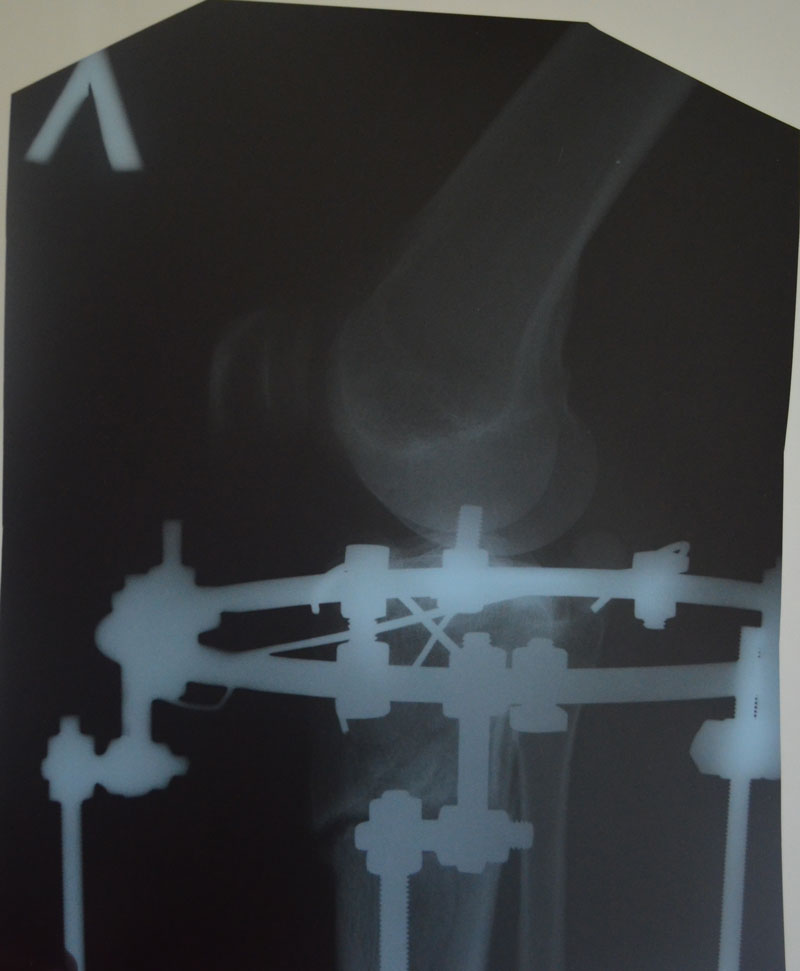

По рентгену, ось ровнейшая. Правая срослась, а левая... Ходить Вам ещё минимум 3 недели, после делайте ещё рентген и отправляйте по эл. почте. Начинайте принимать препараты кальция и мумиё - его нужно принимать так: развести в 0,5 л. банке 10 таблеток - мумиё, до полного растворения таблеток. После этого, принимать по 1 ст. ложки раствора 3 раза в день. Хранить в холодильнике.

Дата операции 28.01.2014г.

Дата снятия аппаратов 06.05.2014г.

Срок лечения 95 дней.